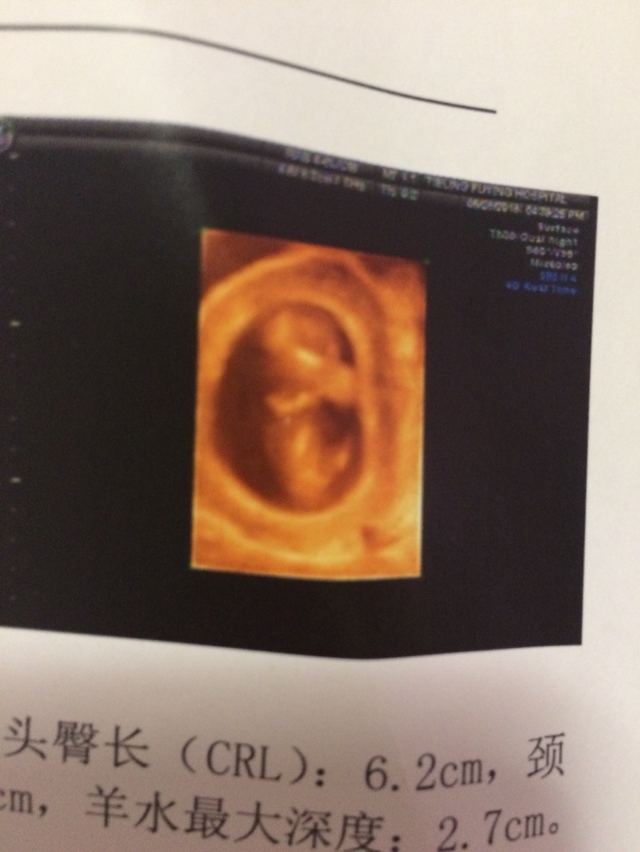

孕15周+2天

看得出来就神了